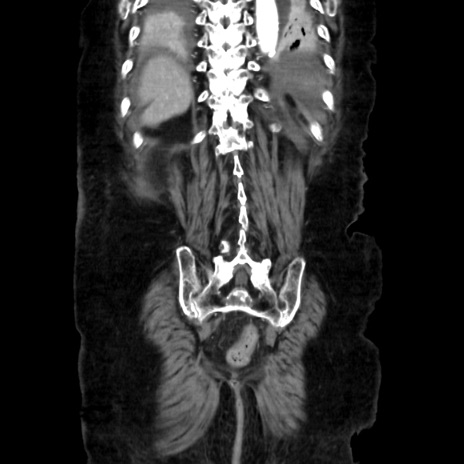

症例40(冠状断像)

矢状断像